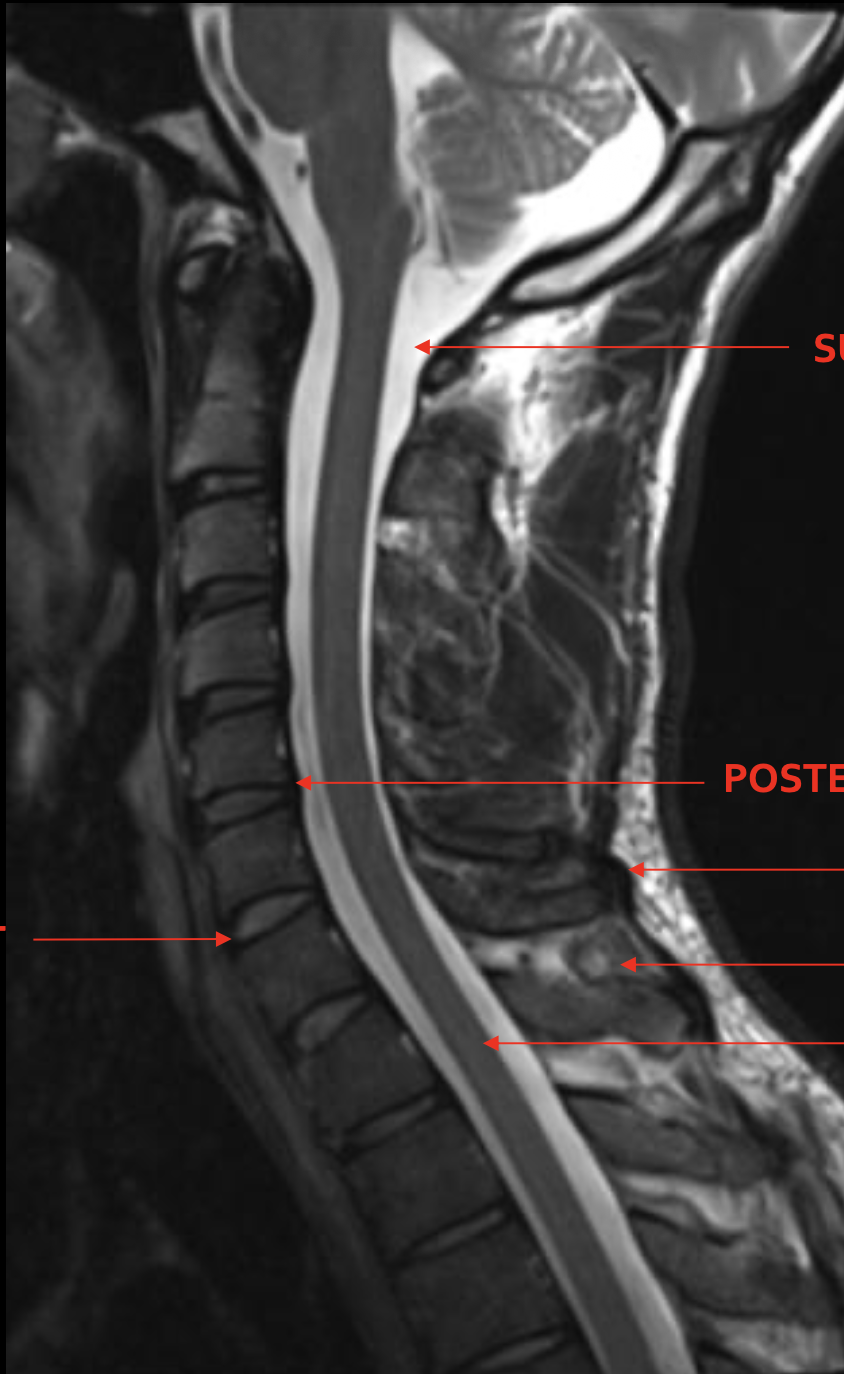

蛛网膜下腔

Subarachnoid space

脊髓

Spinal cord

前纵韧带

Anterior longitudinal ligament (ALL)

后纵韧带

Posterior longitudinal ligament (PLL)

颈深筋膜

Cervical fascia

棘间韧带

Interspinales